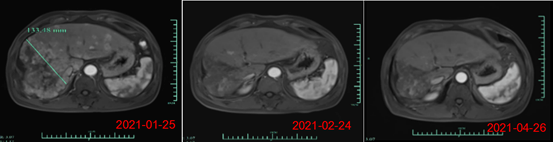

其中,受試者007的PR緩解時(shí)間超過(guò)6個(gè)月,腫瘤體積減少超過(guò)80%。截止日前該患者的緩解周期已超過(guò)8個(gè)月,仍在持續(xù)隨訪(fǎng)中。另一名療效顯著的受試者012是一位彌漫型、巨塊型晚期的肝癌患者,曾接受過(guò)12次以上的TACE治療,在放療及靶向治療無(wú)效后加入本研究。

回輸28天后MRI結(jié)果顯示最大腫瘤直徑從133mm減少至9mm,縮小超過(guò)93%。目前,該受試者在回輸3個(gè)月后評(píng)估,MRI掃描結(jié)果顯示此腫瘤幾乎消失。相應(yīng)地,回輸28天后其AFP(甲胎蛋白,診斷原發(fā)性肝癌特異性的腫瘤標(biāo)志物)水平從>80000降至1148.9ng/ml,回輸3個(gè)月后降至746.7ng/ml(其正常值是在0-40ng/ml以?xún)?nèi)),展示了Ori-CAR-001在晚期肝癌治療的顯著有效性。